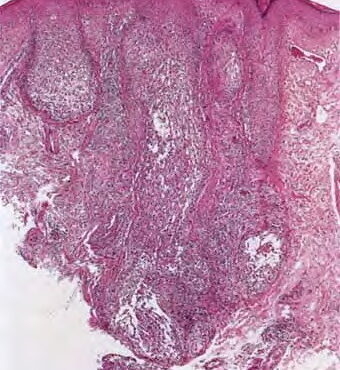

Read MoreAlopecia areata = الحاصة البقعية Alopecia Areata Alopecia areata (AA) is characterized clinically by complete or nearly complete absence of hair in one or more circumscribed areas of the scalp . Clinical inflammation, typically manifested by erythema, is not obvious, and the follicular openings are preserved, a clinical finding that allows the examiner to […]